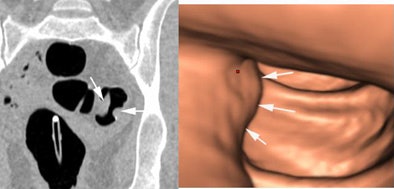

![]() |

| CAD detected the same types of false positives as the unassisted readers. All images and data courtesy of Dr. Stuart Taylor. |